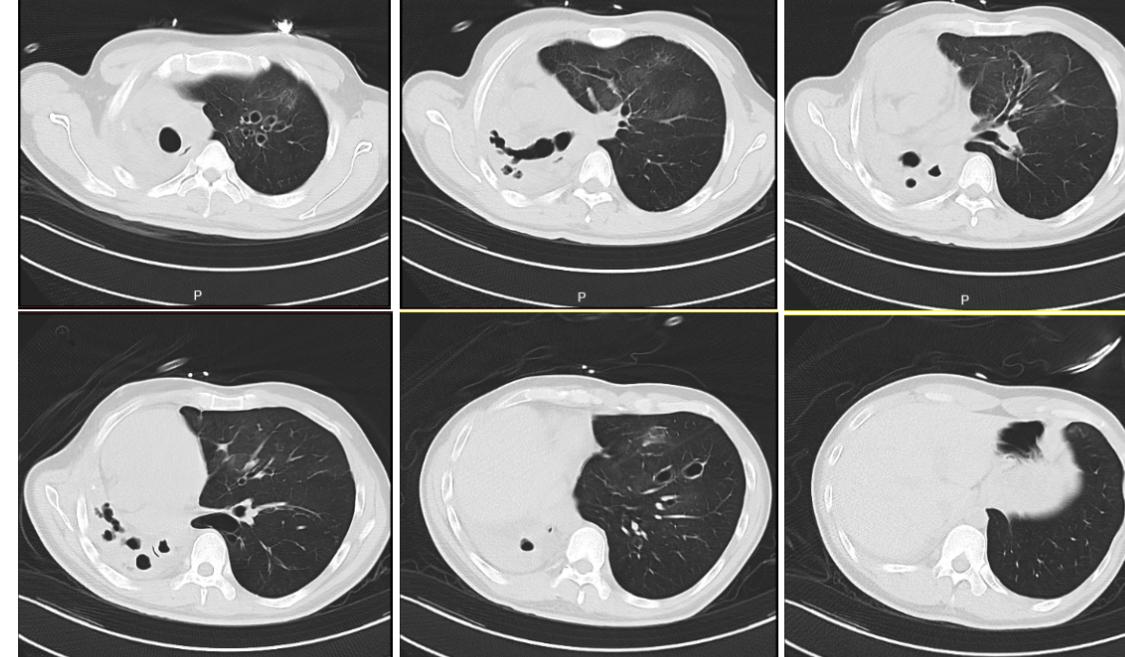

职业病导致的肺损伤,除了晚期尘肺病人做肺移植以外,最近我连续做了3例工作时不慎吸入有毒气体导致的肺损伤肺毁损。这位受者,30岁,吸入硫化氢肺损伤二年了,一直保守治疗,但患者逐渐呼衰,一侧肺毁损、一侧肺气肺。最近在浙二双肺移植术后仅二天,就己行走进行康复锻练,这类受者因为年轻,如果早点接受移植,大都能快速康复。但最近ICU又收治了一位受者,吸入“氟中毒”肺实变纤维化(图4),目前ECMO已维持一个月才想到来求助肺移植,目前濒危,可能会等不到供肺,没有机会救治。

职业病导致的肺损伤,除了晚期尘肺病人做肺移植以外,最近我连续做了3例工作时不慎吸入有毒气体导致的肺损伤肺毁损。这位受者,30岁,吸入硫化氢肺损伤二年了,一直保守治疗,但患者逐渐呼衰,一侧肺毁损、一侧肺气肺。最近在浙二双肺移植术后仅二天,就己行走进行康复锻练,这类受者因为年轻,如果早点接受移植,大都能快速康复。但最近ICU又收治了一位受者,吸入“氟中毒”肺实变纤维化(图4),目前ECMO已维持一个月才想到来求助肺移植,目前濒危,可能会等不到供肺,没有机会救治。